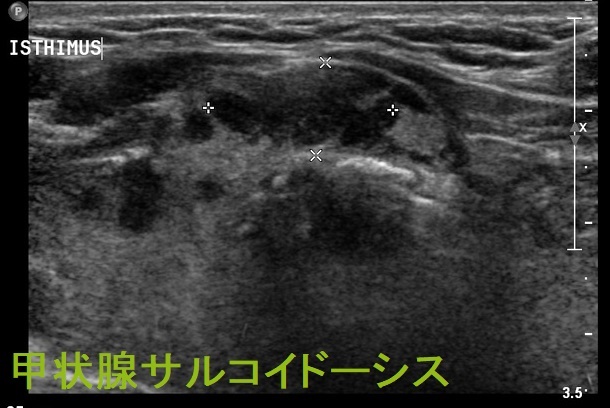

甲状腺サルコイドーシス 超音波(エコー)画像(Radiopaediaより)

甲状腺サルコイドーシスのエコー所見は、不整形の低エコー領域で、甲状腺悪性リンパ腫に類似しています。(写真は日呼吸会誌 2008; 46(8): 667-672.より)